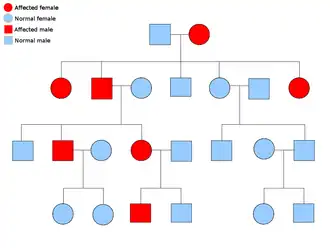

A malignant peripheral nerve sheath tumor is rare, but is one of the most common frequent soft tissue sarcoma in the pediatric population. About half of these cases also happen to occur along with neurofibromatosis type 1 (NF-1), which is a genetic mutation on the 17th chromosome which causes tumors along the nervous system. The lifetime risk of patients with NF-1 developing MPNST has been estimated at 8–13%, while those with only MPNST have a 0.001% in the general population.[4] NF-1 and MPNST are categorized as autosomal dominant disorders. This means when one receives an abnormal gene from one of their parents, they will ultimately have that disorder. That person has a 50/50 chance of passing on that gene to their offspring. The pedigree to the right describes this genetic pattern.